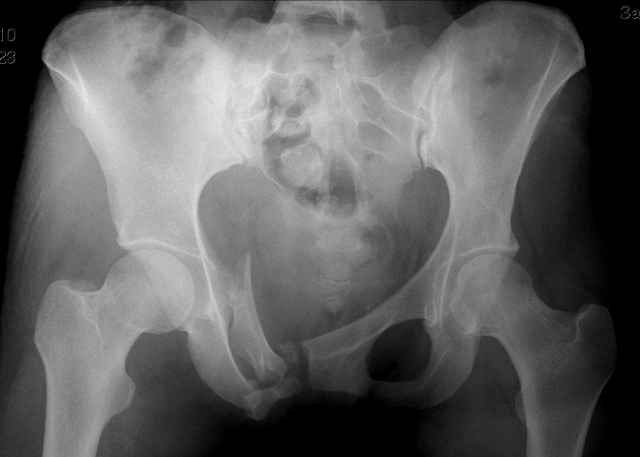

Уважаемые коллеги! Такой вот перелом у пациентки 24 лет.

Проблем с тазовыми органами нет. Как лучше фиксировать? перекрывать пластиной симфиз? Рентгенограмма в приложении.